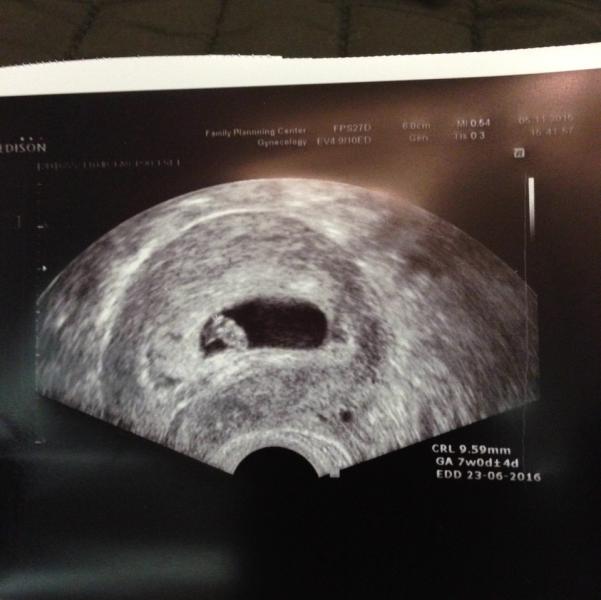

Мне на узи поставили срок день в день как по месячным, на сегодняшний день 7 недель и 1 день, пдр 25 июня, а предполагаемого зачатие 3 октября))) сердце 117 уд/мин.

@jusik, у нас ПДР тоже 23.06! Хотя зачатие было не раньше 30.09!

@darina81, да!!! У нас 23.06.16 )))) а зачатие было 25 сентября, я вот думаю было бы здорово 25 июня родить, это мой день рождения)))

@jusik, у нас пдр почти совпадает, у меня 21.06.16 😊. У вас на УЗИ увидела )